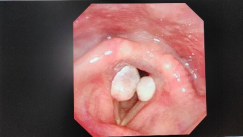

声带肉芽肿

3. 喉镜检查:通过喉镜,医生可以直接观察声带,确认是否存在肉芽肿。